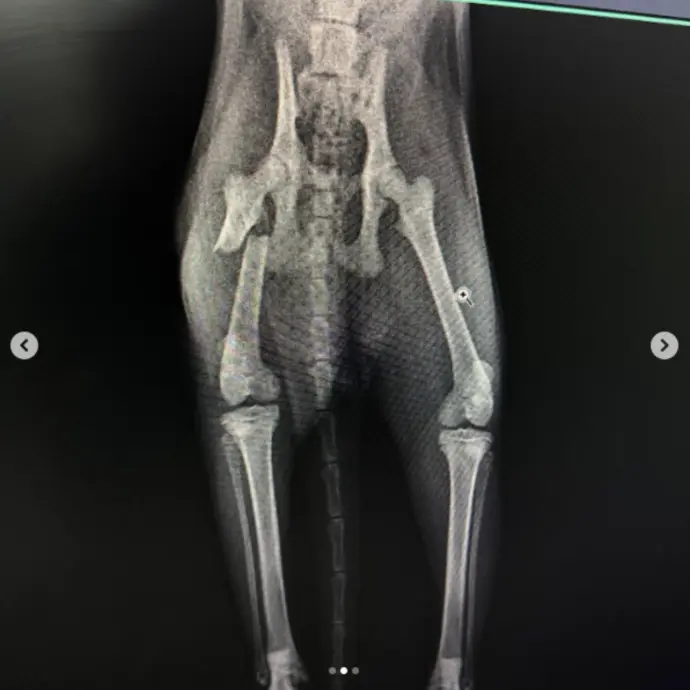

Köpeklerde Diz Kapağı Çıkığı, Çapraz Bağ Kopuğu, Kalça Çıkığı ve Kırık Ameliyatı

Uzmanlık alanları arasında bacak ve kol kırıkları, travma sonucu kalça kırıkları, yüksekten düşme sonucu oluşan travmalar, kranial ve ön çapraz bağ kopmaları, parçalı pelvis kırıkları, eklemden kırıklar, kalça çıkıkları, distal radius ve ulna kırıkları ile doğumsal kalça problemleri gibi birçok ortopedik vaka yer almaktadır.